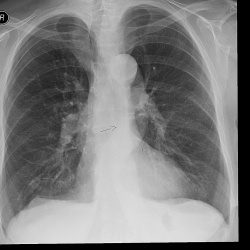

Здравствуйте, уважаемые коллеги. Требуется помощь в интерпретации клинического случая. Женщина 1955гр, работающая, заболела месяц назад- клиника ОРВИ. По снимкам, выполненным в другом леч....